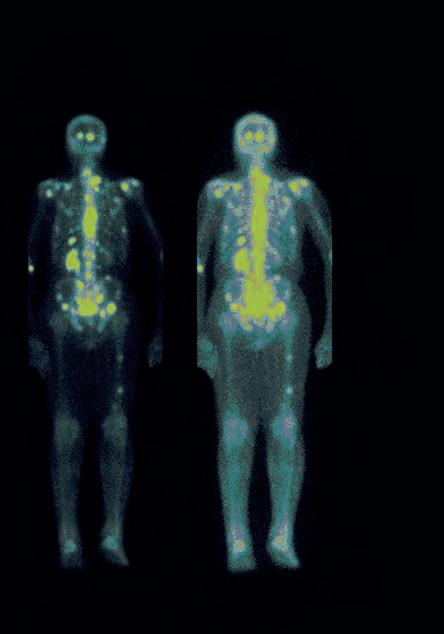

We ask seven experts what the future holds for artificial intelligence (AI) in relation to medical physics and clinical engineering. Questions range from the new standard framework BS 30440, to regulation and AI’s impact on our current and future workforce needs.

RICHARD

While the first AI-driven tools are starting to appear in a wide range of clinical applications, medical physicists/clinical engineers are rarely the intended primary users. In nuclear medicine at least, I am yet to see the wide availability and adoption of AI-driven tools that serve the needs of our workflows. It would be great to see this change, as AI in the form of machine learning is just a tool, freely available for anyone to use in developing solutions to their problems to improve their workflows and patient outcomes.

Currently, clinical scientific computing (CSC) teams work on, for example, data curation and product monitoring, which can be effort and time intensive. In the future, AI may, in part, automate those processes, such as the curation of physiological measurements via a large language model or the quality assurance/quality control of PET/CT systems conducted by AI watchdogs as part of an AI-driven evaluation project overseen by a CSC team.